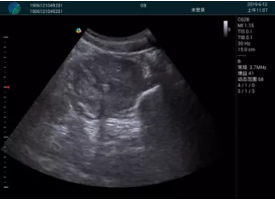

急診醫學(xué)的核心任務(wù)是對危重急的病人進(jìn)行快速診斷并進(jìn)行生命支持,在病人處理中的時(shí)效性和整體性顯得尤為重要。時(shí)效性是指要迅速及時(shí)的對病人的狀況作出初步診斷,同時(shí)采取相應的有效措施,以挽救病人的生命。高效率的緊急救援,是政府機關(guān)、醫院對外形象展示的重要窗口,是衡量一個(gè)地區醫療技術(shù)及管理水平的重要標志。為了適應新時(shí)代急救系統的發(fā)展,新設備新技術(shù)在急救系統的應用顯得越來(lái)越急迫??颠_i-M20便攜平板彩色超聲作為一種快速、無(wú)創(chuàng )的檢測設備在急救系統的應用越來(lái)越普遍。